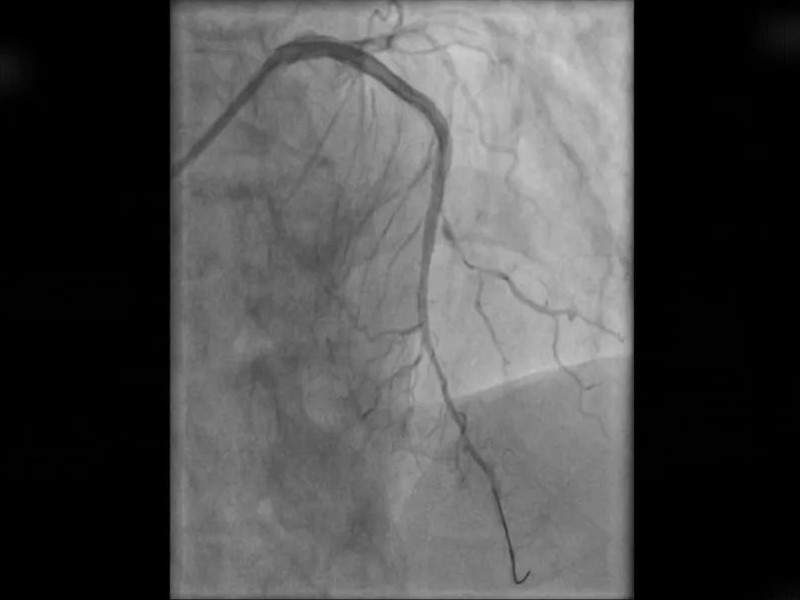

鉴于李先生仍有明显的闷胀性胸痛症状,吉心心内科团队立即启动急诊通道,将其直接送入导管室进行紧急手术。术中发现,患者左前降支血管狭窄程度高达99%,薛国宏医生迅速开通闭塞血管,并成功植入两枚支架。